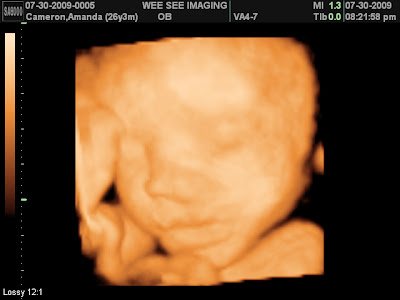

We went to have our 4D ultrasound last night and see Owen, our third gift from God. A 4D ultrasound lets you see them in their full form, not just a black screen. You get to see them do everything they normally do in the womb, just in actual view. He smiled at us, it even looked like he was laughing. He yawned and put on a big show. He is so handsome. He looks a little like Evan to me. Full lips and pudgy nose! He weighs about 2.25 pounds right now and is measuring right on time for a late October birth! I am going to show a few pictures.

Here is some pictures of our little guy!

The first one is his face, the second is of him yawning, the third is him laughing and the last one is him with his face in his hands.